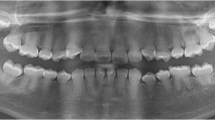

A 24-year-old woman was referred from a private dental clinic to the dental hospital due to recurrent swelling and pain in the vestibular region of teeth 23-25 despite receiving endodontic treatment over the past two weeks. Medical and family history were noncontributory. The extraoral examination showed no apparent abnormalities. The intraoral examination revealed temporary sealing materials on the occlusal surface of teeth 24 and 25 (Fig. 1B, green arrow). Compared with the contralateral canine, tooth 23 exhibited a larger mesiodistal diameter (Fig. 1A) and had a small pit on the mesial part of the palatal surface of tooth 23 (Fig. 1B, black arrow). For teeth 23-25, there was no evidence of caries, restorations, increased tooth mobility, or increased probing depth. Pulp sensibility tests indicated no response to cold/hot or electric pulp tests. Some discomfort was experienced on direct vertical percussion, and slight pain was felt upon palpation of the periapical area. The buccal/labial alveolar mucosa related to teeth 23-25 was normal, with no swelling or sinus tract (Fig. 1C). The periapical radiograph (Fig. 1D) revealed Oehlers’ Type II CDI in tooth 23 and a radiolucent lesion in the periapical region of teeth 23-25. To elucidate the morphology of tooth 23 and the extent of the periapical radiolucency [15, 16], a CBCT scan (Morita, Kyoto, Japan) was taken with a voxel size of 125 μm and exposure parameters of 90 kV, 5.0 mA and 17.5 s with the patient's consent. The CBCT scan revealed the following findings: 1) The upper half of the invagination was tooth-shaped and highly compressed the true root canal into a crescent shape, while the lower half was irregularly cylindrical and compressed the root canal into a ring. 2) The periapical radiolucency extended from the mesial side of tooth 23 to the distal side of tooth 25 and involved the buccal wall of the alveolar bone but was not connected to the maxillary sinus. 3) A lateral perforation was observed on the mesial wall of the pulp cavity of tooth 24 (Fig. 1E-G). Three-dimensional reconstruction images of the complex canal morphology of tooth 23 using Mimics 19.0 (Materialise, Belgium) were shown in Figure 2A-B.

Preoperative examination of case 1. A Tooth 23 exhibited a larger mesiodistal diameter than tooth 13. B Green arrow: temporary sealing material on the occlusal surface of teeth 24 and 25; black arrow: a small foramen caecum on the mesial part of the palatal surface of tooth 23. C No swelling or sinus tract was observed at the buccal/labial alveolar mucosa related to teeth 23-25. D The periapical radiograph revealed CDI in tooth 23 and a radiolucent lesion in the periapical region of teeth 23-25. E-G CBCT scan images: E Axial slices at various points denoted on the sagittal section. The upper half of the invagination appeared tooth-shaped, compressing the true root canal into a crescent, while the lower half showed an irregularly cylindrical shape, compressing the true root canal into a ring. F The periapical radiolucency extended from the mesial side of tooth 23 to the distal side of tooth 25. G A lateral perforation on the mesial wall of tooth 24

A 39-year-old woman was referred to the hospital due to pain in the left upper anterior tooth after crown preparation to correct tooth discoloration. Medical and family history were non-contributory. The extraoral examination revealed no apparent abnormalities, and the intraoral examination revealed crown preparation of tooth 22, along with an access cavity in the middle of its palatal surface (Fig. 4A, B, white arrow). There was no tooth mobility or increased probing depth. Pulp sensibility tests indicated no response to cold/hot or electric pulp tests. The tooth exhibited intense discomfort on direct vertical percussion and pain upon palpation of the periapical area. Radiographic examination revealed Oehlers’ Type II CDI in tooth 22. The upper half of the invagination was tooth-shaped and highly compressed the true root canal into a ring, while the lower half was irregularly cylindrical and compressed the root canal into a crescent shape. The periodontal ligament space was widened (Fig. 4C, D). Three-dimensional reconstruction images depicted the complex canal morphology of tooth 22 (Fig. 4E). The diagnosis was Type II CDI with acute apical periodontitis. Four debridement routes were designed, and corresponding templates were fabricated (Fig. 4F, G). GE-based RCT was implemented using the same procedure as described in case 1 (bur: TF-11, MANI, Utsunomiya, Japan; Fig. 4H-K). The three-year follow-up showed no obvious abnormalities, and the treated tooth was asymptomatic (Fig. 4L, M and Fig. S2).

Treatment process and follow-up of Case 2. A, B Preoperative intraoral examination. C, D Preoperative periapical radiograph and CBCT scans. E Three-dimensional reconstruction of tooth 22 and virtual simulation of four debridement routes designed based on the MICRO principle. F, G Procedure for fabricating the templates. H, I Four opening access cavities guided by templates. J, K After root canal filling, the effect was verified. L, M 3-year follow-up